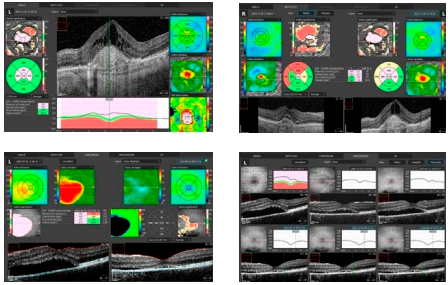

- анализ сетчатки – исследуются толщины сетчатки, комплекса GCL+IPL, комплекса RNFL+GCL+IPL, деформация RPE, толщины RNFL и RPE, девиация относительно НБД;

- анализ глаукомный – исследуются морфология ДЗН, RNFL, DDLS, анализируются клетки ганглиозные в комплексах RNFL+GCL+IPL/GCL+IPL, производится анализ симметрии и прогрессии;

- анализ переднего отрезка глаза – включает пахиметрию, карту эпителия, LASIK flap; производятся анализ угла и коррекция ВГД для пневмотонометрии.

Различные средства для исследования глаукомы, для анализа количественных характеристик слоя нервных волокон, ганглиозных клеток и вершины оптического нерва с составлением шкалы возможности дефекта диска дают возможность максимально точно провести анализ и слежение за течением глаукомы во времени.

Cетчатка

Одно отсканированное изображение макулы в 3D позволяет провести диагностику сетчатки и глаукомы. ПО в автоматическом режиме различает 8 слоев сетчатки, это необходимо для качественного исследования и формирования диаграммы изменений в здоровье больного человека. Наличие совершенно разных методик обработки результатов и презентации дает возможность отдать предпочтение наиболее действенной для пациента, увеличивая эффективность работы.